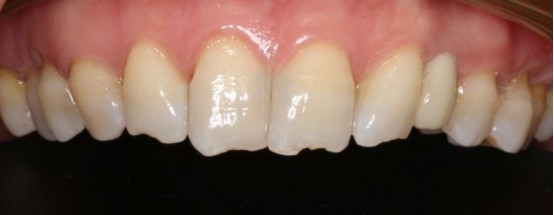

2. 23左上尖牙属于美学区种植,对牙齿的外观、色泽、饱和度等有较高要求。

通过这个案例,我们可以看到,尽管尖牙区种植具有一定的挑战性,但通过精确的术前评估和手术设计,我们可以取得良好的治疗效果。